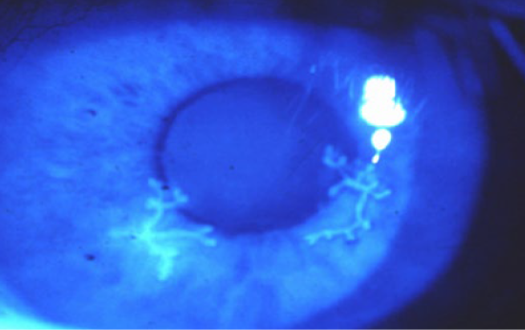

角膜ヘルペス

ウイルスが角膜の上皮で増えて、樹木の枝のように見えるので、樹枝状角膜炎と呼ばれます。

充血・痛み・まぶしいなどの症状が現れます。病変が急激に広がって見えにくくなることもありますので、注意が必要です。(地図状角膜炎)